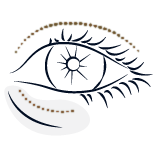

Parpados y Bolsas (Blefaroplastia)

CIRUGÍA FACIAL

Eliminación las bolsas de los ojos, los párpados superiores caídos y mejorar la armonía del rostro